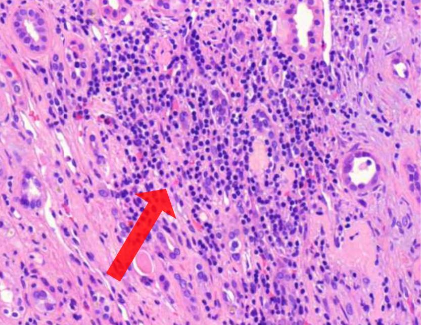

Aktiinikeratoosi

päättele kuvien ja tekstien avulla, mikä tauti on kyseessä?

Dysplasiaan

mihin viittaavat seuraavat mitoosit? (vinkki: aktiinikeratoosi)

Huulen levyepiteelikarsinooma

seuraavan kuvan ja tekstien avulla, mikä tauti on kyseessä?